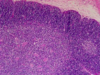

What do the arrows in this picture indicate?

Left = ileum

Middle = villi

Right = lymphoid tissue